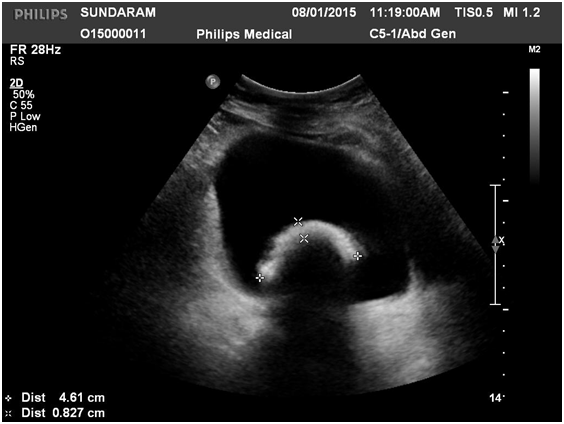

On initial evaluation with ultrasound (Figure 1) revealed a vesical calculus. On further evaluation with X-ray KUB (Figure 2) and CT Scan (Figure 3) (Figure 4) showed large laminated vesical calculus and Copper T seen outside the uterus with horizontal portion in the vesicouterine pouch, long vertical portion seen protruding into the urinary bladder lumen through the posterior wall partly encased in the vesical calculus.

Figure 4 CT Showing Copper T Horizontal limb in Vesicouterine pouch.

The diagnosis of the migration is usually by either an ultrasonography or Plain X-ray KUB region. CT scan helps to clearly delineate the exact location of the foreign body as in the present case. Cystoscopy is useful in case of radiolucent foreign body such as Mesh.